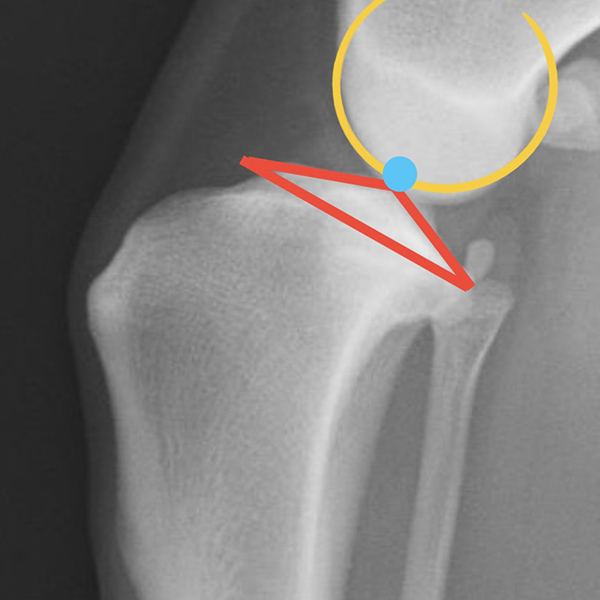

X線検査

レントゲン検査では、大腿骨と脛骨の位置関係や関節包の腫れ、腫瘍性疾患の存在を示唆する骨吸収像の有無などを確認します。写真の○と△は大腿骨と脛骨の位置関係を示しています。正常な位置関係では△の青丸と○の青丸が重なるように位置していますが、靭帯断裂症例では、両者の青丸がズレていることが確認できます。